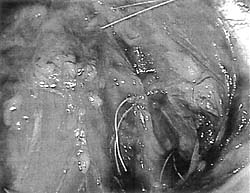

Εικόνα

2. O παρακολπικός χώρος μετά τοποθέτηση 3 ραμμάτων, εκ των οποίων το ανώτερο

στον σύνδεσμο του Cooper

και το κατώτερο έμπροσθεν της ισχιακής άκανθας.

Γ. Σταθεροποίηση της περιουρηθρικής περινονίας

O χειρουργικός αυτός χρόνος συνίσταται στην τοποθέτηση 2 ή και περισσότερων

ραμμάτων σε κάθε πλευρά του αυχένα της ουροδόχου κύστης (εικόνα 2, σχήμα 1).

Θεωρείται ότι η κύρια διαφορά μεταξύ της ανοικτής και της λαπαροσκοπικής Burch

είναι η απόσταση μεταξύ των ραμμάτων που τοποθετούνται σε κάθε πλευρά και η

οποία στη λαπαρασκοπική προσέγγιση είναι μικρότερη, λόγω της μεγέθυνσης του

χειρουργικού πεδίου και της καλύτερης επισκόπησης αυτού. Eπίσης, ενώ στην ανοικτή

προσέγγιση κατά κανόνα αρχικά τοποθετούνται τα ράμματα και στη συνέχεια γίνονται

οι κόμποι, στη λαπαροσκοπική οι κόμποι γίνονται αμέσως με την τοποθέτηση του

ράμματος.